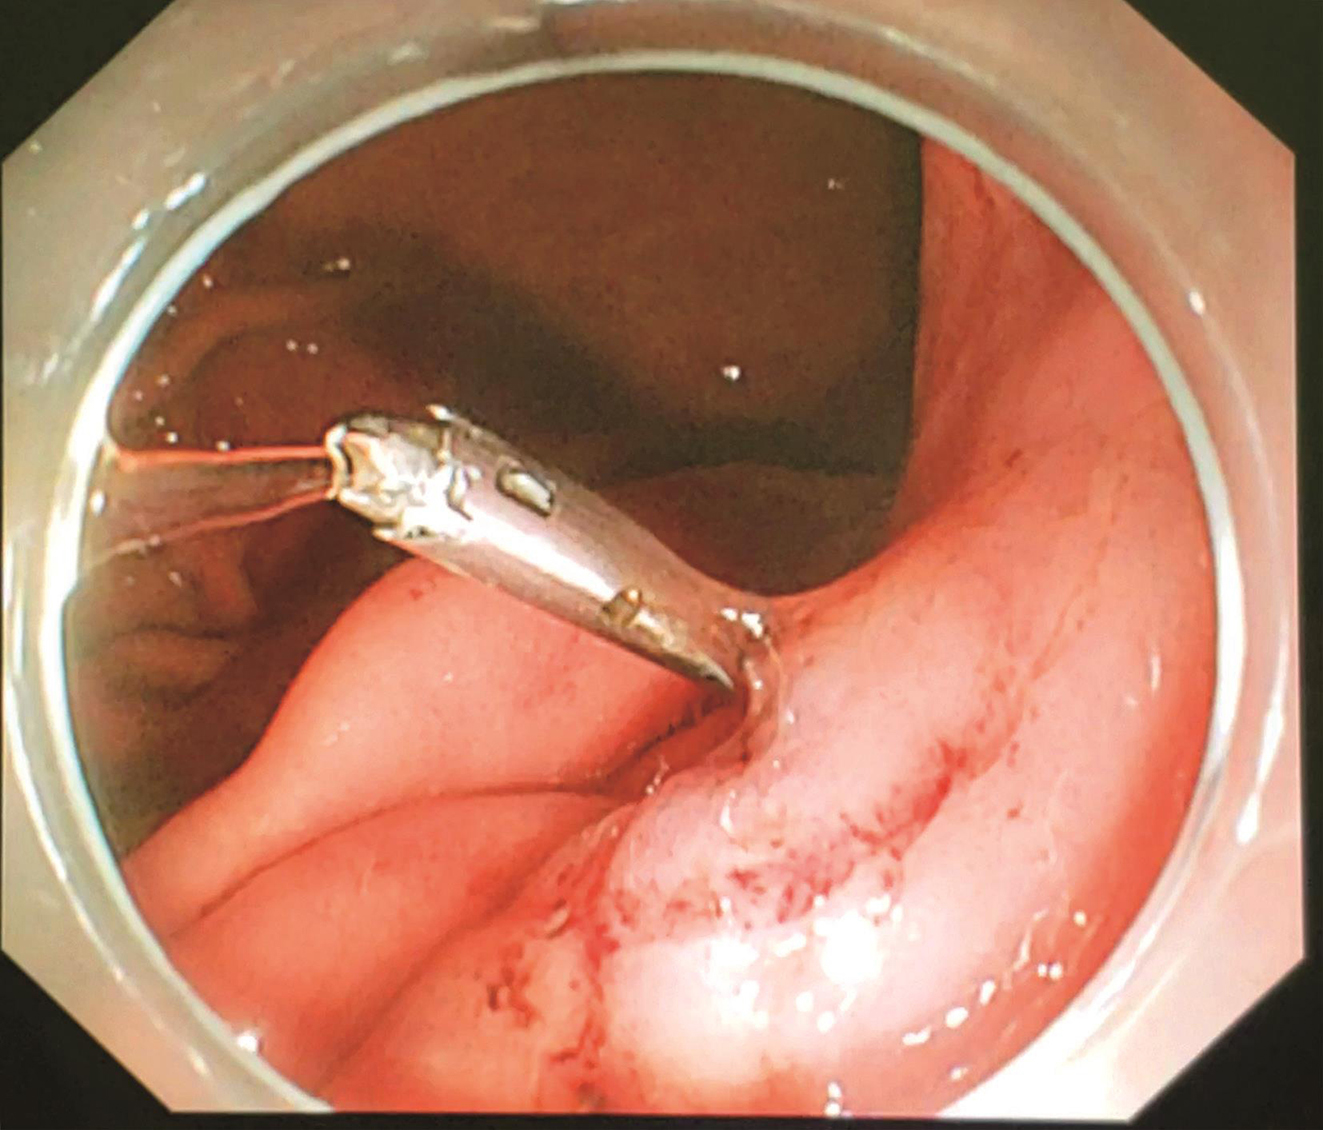

患者于2018年08月30日接受“腹腔镜+胃镜双镜联合胃肿瘤切除术”,胃肠外科与消化科医师共同上台。术中内镜见胃体小弯侧后壁直径4cm黏膜下肿瘤,腔内生长,未侵犯胃黏膜及浆膜(图3),胃周淋巴结无肿大,小网膜囊内可及直径1cm钙化脂肪结节一枚,肝脏、盆腔、腹膜未及转移灶。经口置入内镜,探查肿瘤,于肿瘤边缘黏膜下注水(图4);内镜指引下,腹腔镜下以超声刀距肿瘤边缘1cm切开胃壁浆膜,沿肿瘤包膜外,全层切开胃壁,完整切除肿瘤(图5);以3-0可吸收线间断全层缝合胃壁缺损;术中胃镜检查胃创面;创面部分黏膜缺损处内镜下以钛夹封闭(图6);肿瘤标本置于标本袋内,经脐部戳孔处取出(图7)。

图4 术中内镜下于肿瘤边缘黏膜下注水